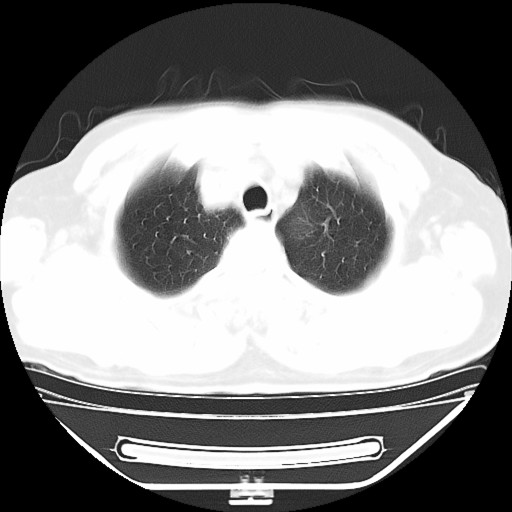

以下是引用hhcckk在2009-5-29 10:34:00的发言:[br]左下肺片絮状边缘模糊影,考虑感染,建议治疗后复查[br]